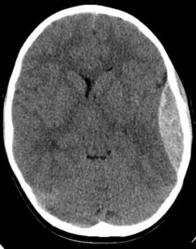

This case-based presentation demonstrates the connection between somatic dysfunction and symptom presentation in an individual with recurrent subdural hemorrhaging. Additionally, you will learn about the incredible utility of OMM in healing the body and providing patient-centered care.